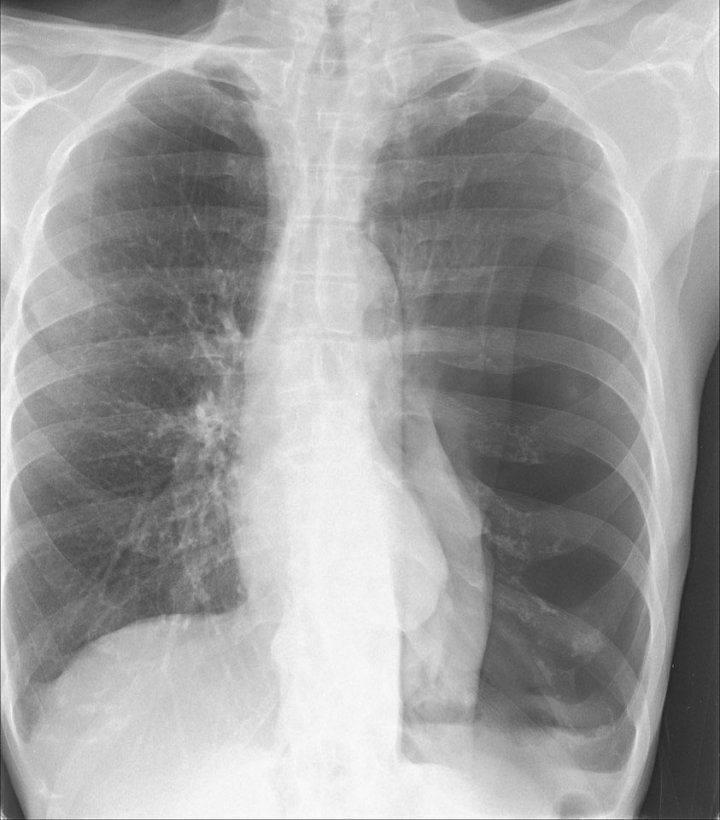

Chest X-ray showing collapsed lung, or pneumothorax.

Image courtesy of Rachael Callcut, MD